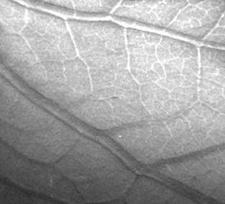

где a - угол между пучком и преломляющей поверхностью, n - показатель преломления, l - длина волны, выраженная в ангстремах. Величина рефракционного контраста определяется относительным локальным изменением интенсивности пучка, испытавшего отклонение на угол a. Для цилиндрического объекта наибольший контраст возникает на его краях, поэтому изображения кажутся объемными (см., например, рис.2). Подробный расчет контраста и дозы облучения для рефракционной интроскопии можно найти в [4].

Рис. 2. Изображение древесного листа,

полученное методом рефракционной интроскопии.